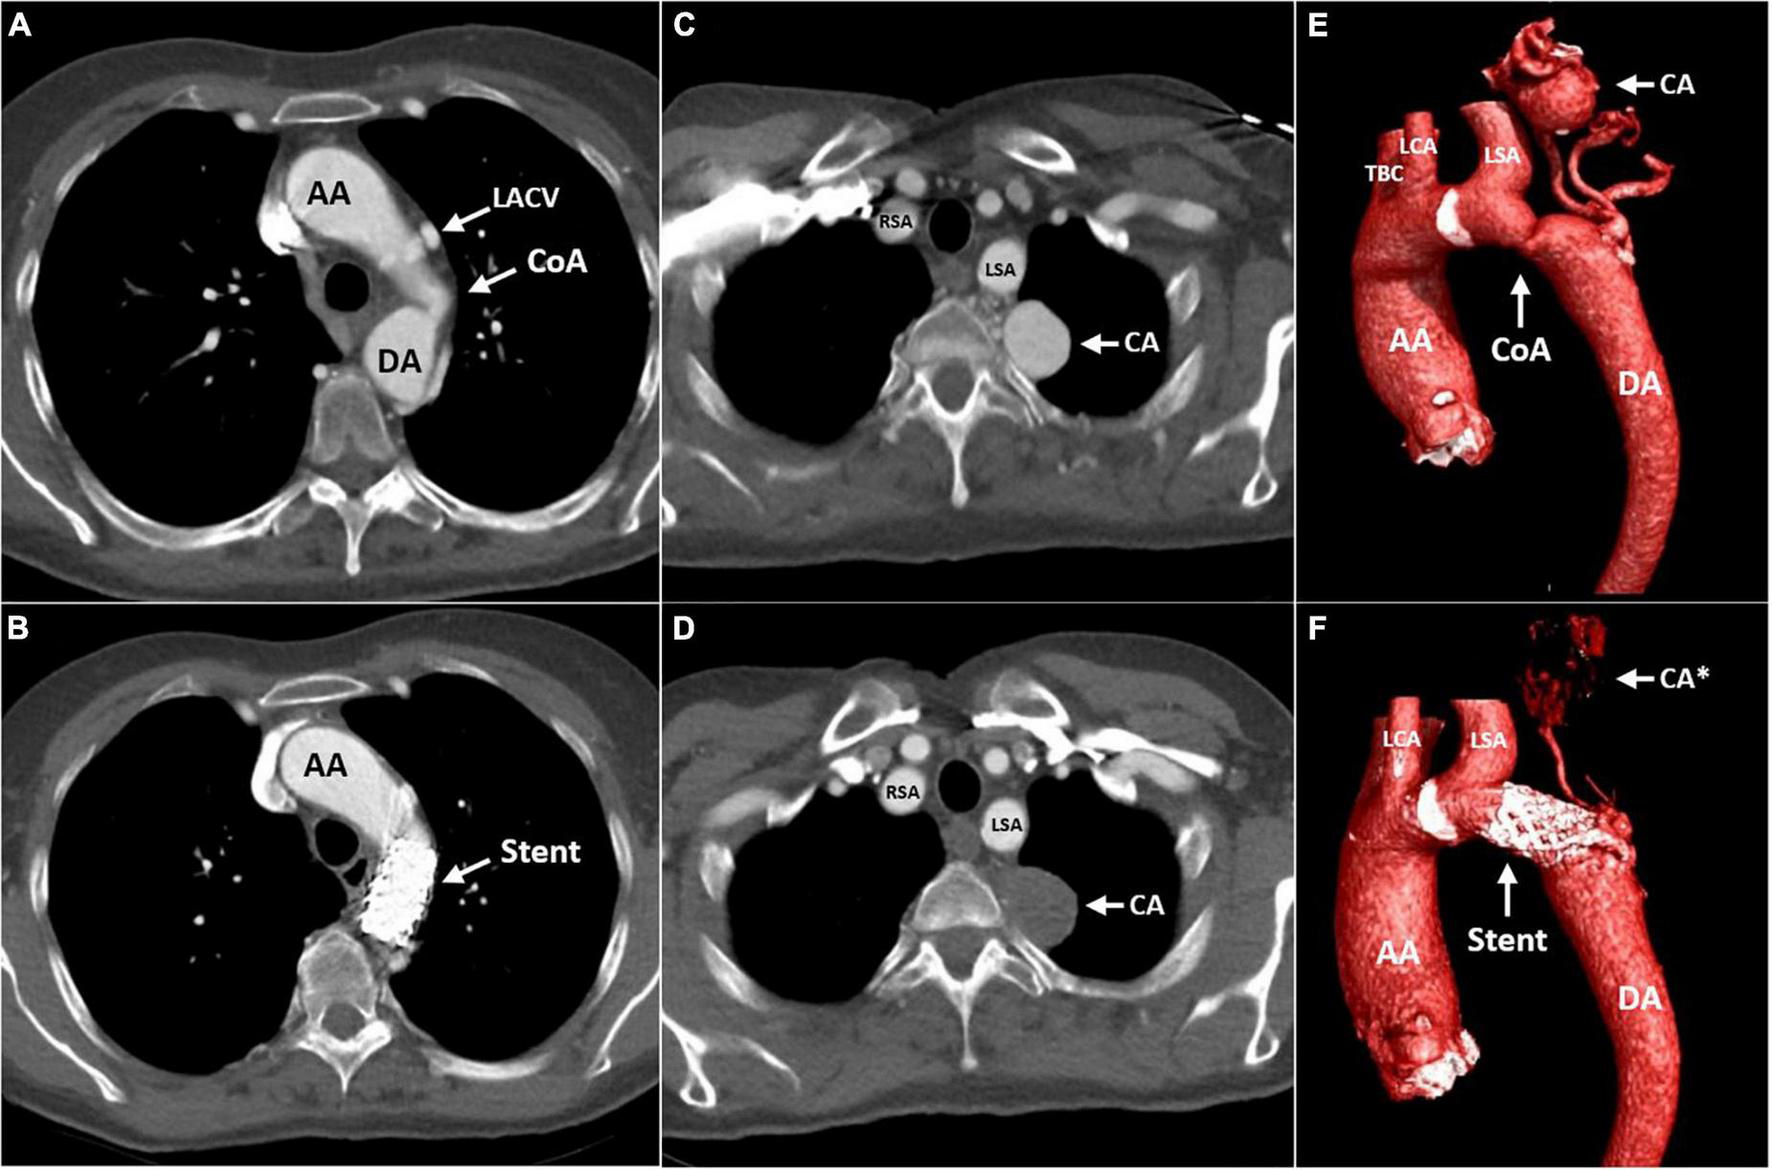

FIGURE 3

Computed tomography (CT) angiography of the aorta before (A,C,E) and 4 months after (B,D,F) implantation of a covered stent across the CoA. The transverse plane is at the level of the CoA (A,B) and the level of the left paravertebral aneurysmatic collateral artery (C,D). Cinematic 3D reconstruction of the thoracic aorta, illustrating the CoA and associated aneurysmatic collateral artery (E,F). AA, ascending aorta; DA, descending aorta; LACV, levoatriocardinal vein; CoA, coarctation of the aorta; Stent, covered stent in the coarctation zone; CA, aneurysmatic collateral artery; CA*, location of the aneurysmatic collateral artery; RSA, right subclavian artery; LSA, left subclavian artery; LCA, left carotid artery; TBC, truncus brachiocephalicus.

A three-dimensional (3D) print of the heart, aorta, and collateral vessels, including the aneurysm, was constructed to facilitate a better understanding of the complex anatomy. The patient was discussed in the adult congenital heart team; considering the patient’s age and the perioperative risk of aortic surgery in the presence of extensive and aneurysmatic collaterals, we pursued a primarily percutaneous strategy. Invasive pressure measurements revealed systolic blood pressures proximal and distal to the CoA of 178 and 95 mmHg, respectively. This resulted in a gradient of 83 mmHg, warranting the indication for intervention. To treat the coarctation, a covered stent was implanted (Figures 4A, B) with good angiographic results and alleviation of the pressure gradient. Figure 4C shows the angiography of the collateral artery aneurysm that was subjected to conservative treatment. Coronary angiography confirmed a significant stenotic lesion in the proximal left anterior descending artery (80–90% stenosis), for which a percutaneous coronary intervention (PCI) with stent implantation was performed. The other coronary arteries showed non-significant atherosclerotic lesions. The post-operative period was uneventful, dual antiplatelet therapy with acetylsalicylic acid and clopidogrel was started, and amlodipine was discontinued. Two months later, losartan was discontinued due to the normalization of blood pressures to 100–125/70 mmHg.

The patient was seen for a follow-up at the outpatient clinic 4 months after the procedure. She was normotensive and reported to be doing well, experiencing no functional limitations during daily activities. Transthoracic echocardiography showed stable dimensions of the ascending aorta, moderate insufficiency of the aortic valve, and preserved left ventricular function. The peak flow velocity over the coarctation was measured as 1.7 m/s, corresponding to a derived pressure gradient of 12 mmHg. CTA confirmed stable aortic dimensions and good position and deployment of the stent at the CoA site. The large collateral artery aneurysm no longer showed any contrast opacification, likely reflecting spontaneous thrombosis secondary to the diminished collateral flow after the alleviation of the coarctation (Figures 3B, D, F).